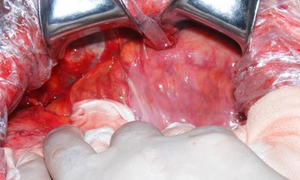

(1)肉眼观:包膜为蚕茧样,壁厚1~10mm,为一层灰白色、乳白色或淡黄色结缔组织,表面光滑,单腔或多房,可包裹部分小肠或全部小肠,甚至可包裹整个腹腔的脏器。整个肿块能活动,不受壁腹膜的影响,肿块与腹膜壁层可有疏松的纤维样结缔组织粘连,易于分离。由于小肠被局限包裹,小肠长度往往较正常短,肠系膜亦较短,并可有肠壁增厚、肠腔狭窄和扩张等。

(2)镜下观:包膜可为正常腹膜样组织,或为增厚的纤维结缔组织。可伴有胶原变化,玻璃样变及慢性炎性反应,非真菌、细菌和寄生虫等微生物感染。

(3)病理组织学检查

大体可见包膜为蚕茧样,为一层灰白色、乳白色或淡黄色结缔组织,可包裹部分小肠或全部小肠,甚至可包裹整个腹腔的脏器。整个肿块能活动,不受壁腹膜的影响,肿块与腹膜壁层可有疏松的纤维样结缔组织粘连,易于分离。小肠长度、肠系膜往往较短,并可有肠壁增厚、肠腔狭窄和扩张等。镜下可示包膜可为正常腹膜样组织,或为增厚的纤维结缔组织。